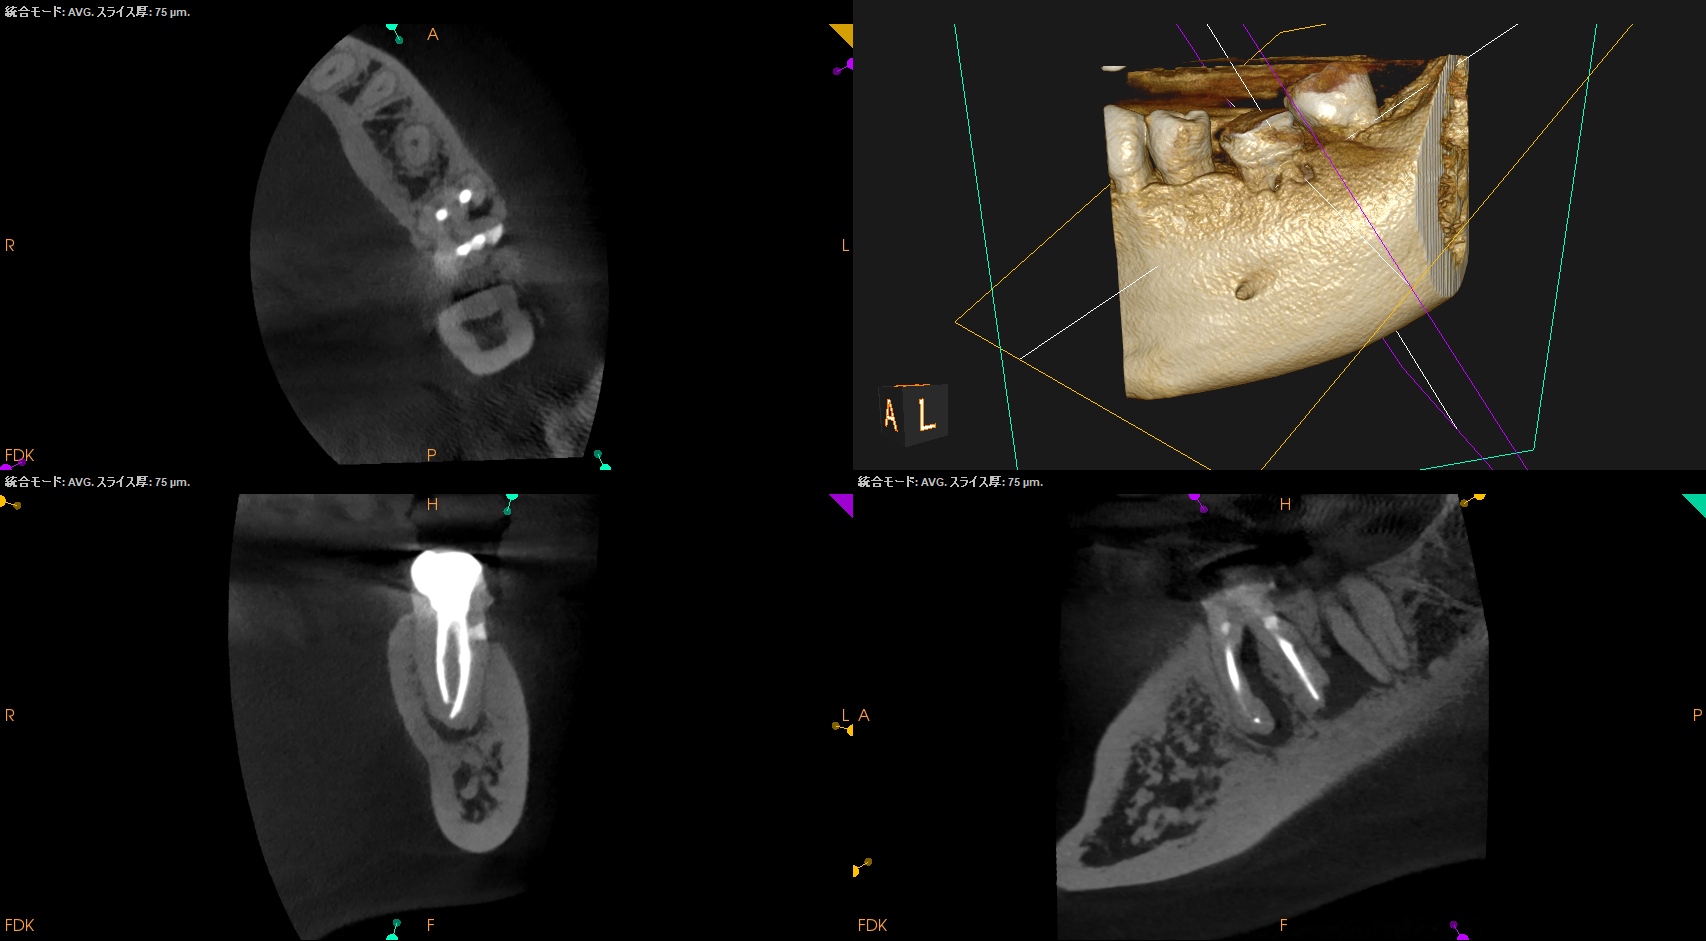

術後にPA, CBCTを撮影した。

MB

ML

DB

DL

B

問題はないだろう。

次回は半年後である。